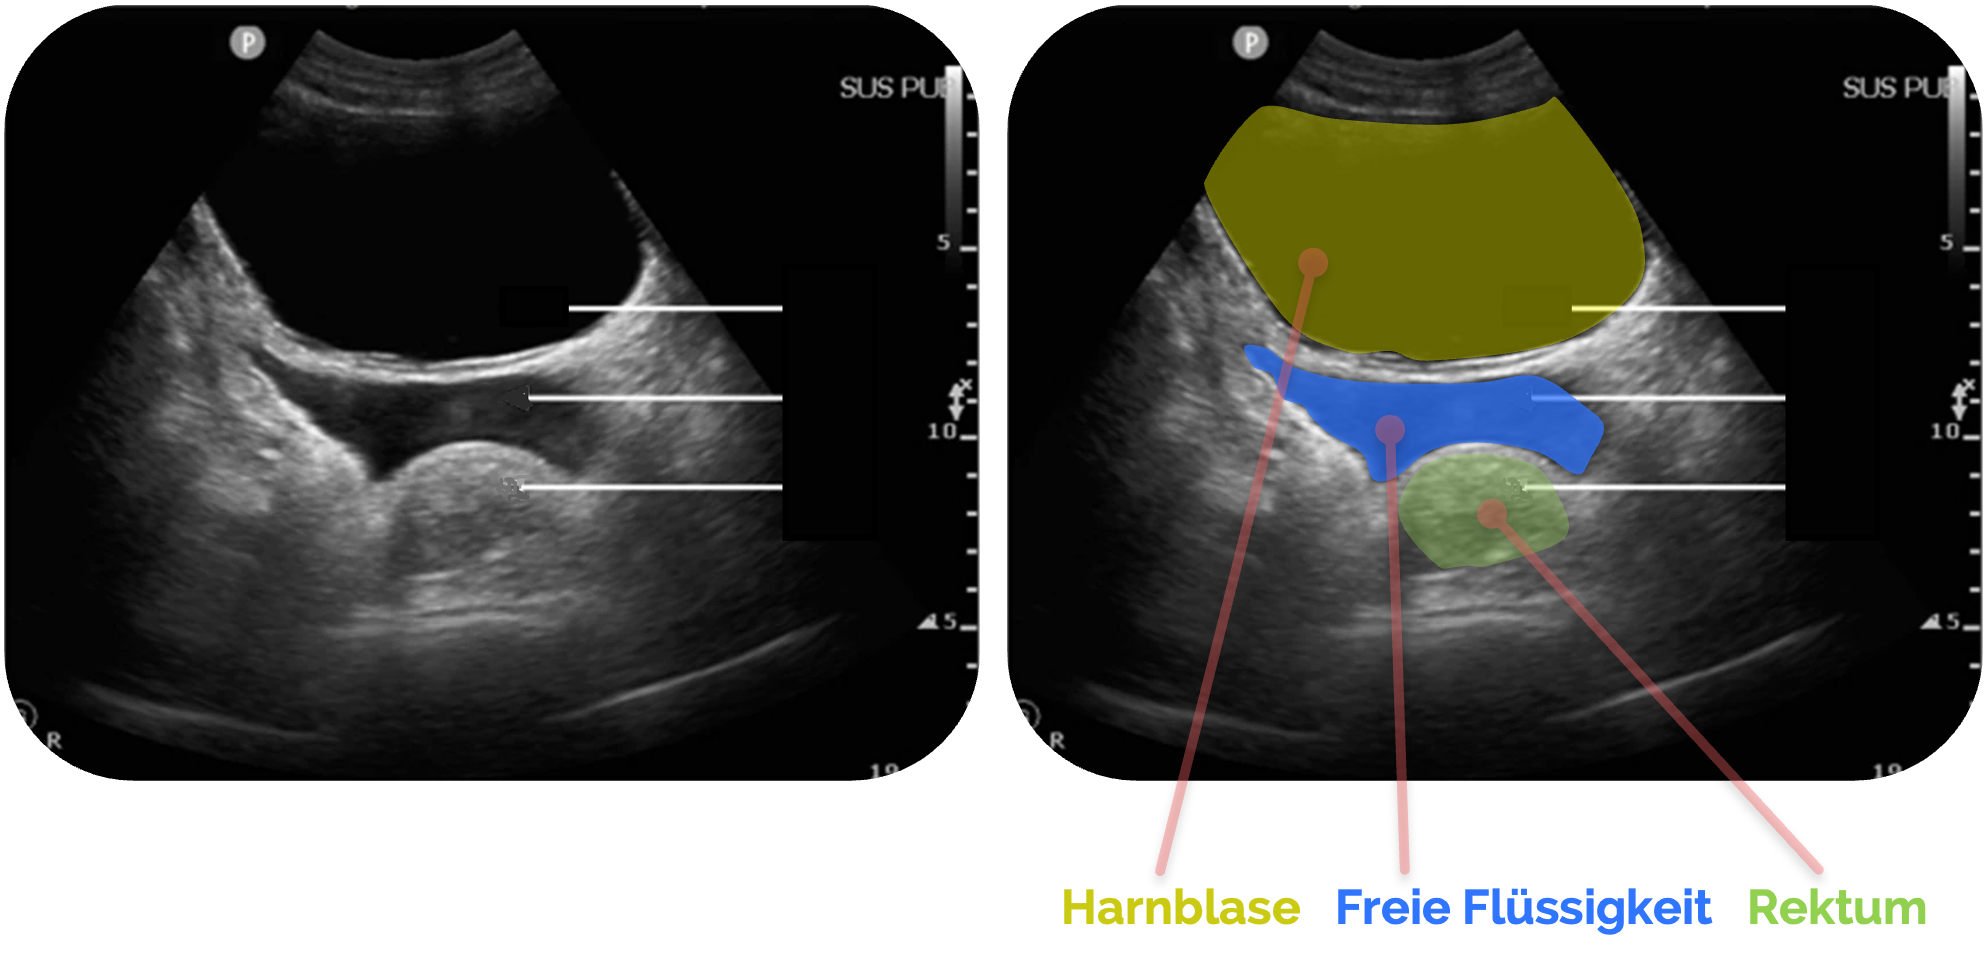

Freie Flüssigkeit beim Mann

Freie Flüssigkeit im Proust-Raum (Excavatio rectovesicalis) beim Mann ist immer als pathologisch zu werten und erfordert in nahezu jedem Fall eine weitergehende Diagnostik.

In der Sonographie zeigt sich freie Flüssigkeit typischerweise als anechogene oder echoarme Zone zwischen Harnblase und Rektum

In Abhängigkeit von der Zusammensetzung kann die Flüssigkeit auch inhomogene oder echoreiche Anteile aufweisen, etwa bei Blutungen oder infektiösem Exsudat

Figure 3 aus Fasseaux, A., Pès, P., Steenebruggen, F. et al. Are seminal vesicles a potential pitfall during pelvic exploration using point-of-care ultrasound (POCUS)?. Ultrasound J 13, 14 (2021). https://doi.org/10.1186/s13089-021-00209-7. Es wurden teilweise die Markierungen und Beschriftungen ergänzt.

Der Proust-Raum ist der tiefste intraperitoneale

Zu den häufigsten Ursachen zählen intraabdominelle Traumata mit Blutungen (z. B. Leber